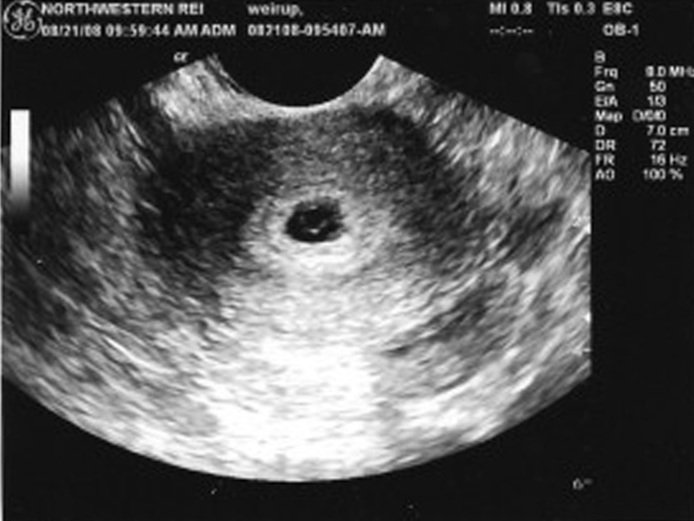

Именно по такому состоянию эндометрия удается диагностировать беременность на очень ранних сроках, то есть тогда, когда плодное яйцо еще не видно. Также этот показатель влияет на диагностику самопроизвольного аборта (выкидыша) на очень ранних сроках. Иногда женщина может такого выкидыша не заметить или не почувствовать, и тогда УЗИ, в ходе которого диагностируются изменения, подтверждает сам факт наличия беременности несколько дней назад.

- Ультразвуковое исследование, на котором визуализируются толщина и структура эндометрия;